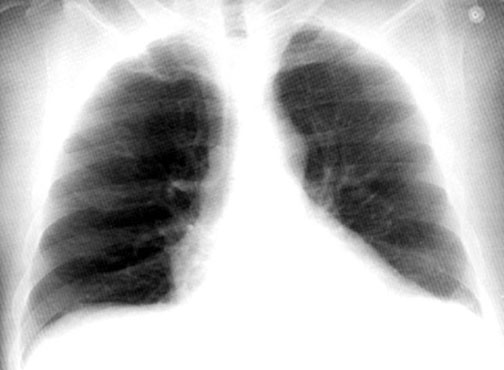

Case 30

Lateral

Initial PA

Initial lateral

Follow up

Labeled Image What are the common segments for aspiration lung abscess?

What are the types of aspiration?